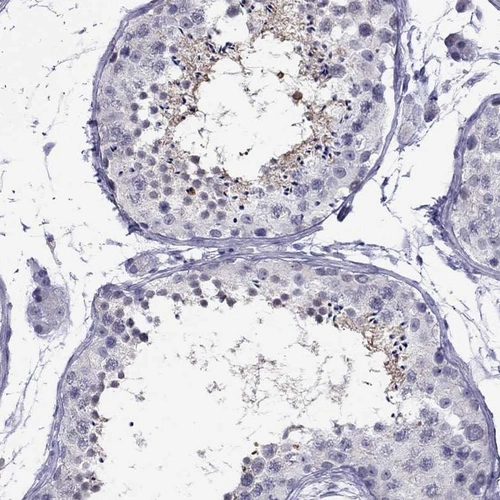

Immunohistochemical staining of human testis shows moderate cytoplasmic positivity in cells in seminiferous ducts.